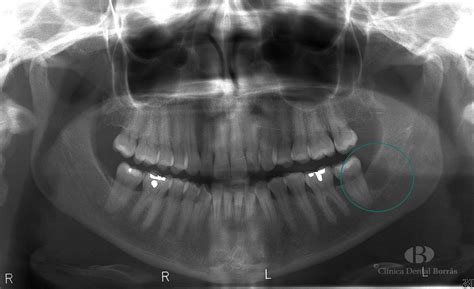

Aunque un médico experimentado puede identificar muchos quistes mediante una simple inspección física y palpación, en ocasiones se requieren pruebas adicionales para confirmar el diagnóstico y asegurar que no se trata de otra patología. Las herramientas de diagnóstico incluyen ecografías, resonancias magnéticas o tomografías computarizadas. En casos donde existe duda sobre el contenido, el médico puede realizar una biopsia o aspiración con aguja fina.